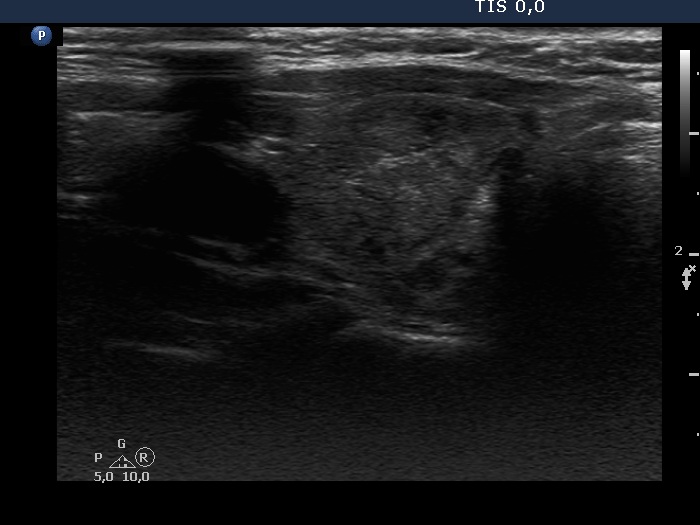

Consecutive patients with the final diagnosis of Hashimoto's thyroiditis - case 5 (1782) (ultrasonographic picture 6)

Left lobe, longitudinal scan.